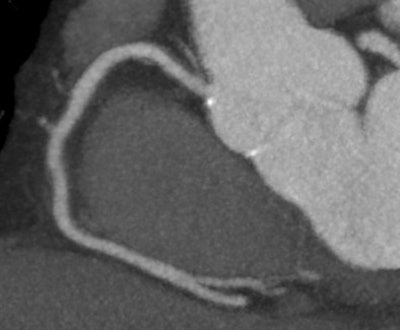

| Example of a 320-row CT scan of a right coronary artery with proximal noncalcified plaque but without significant stenoses in a patient with atrial fibrillation and a heart rate between 75 and 120 beats per minute. Image courtesy of Dr. Marc Dewey. |